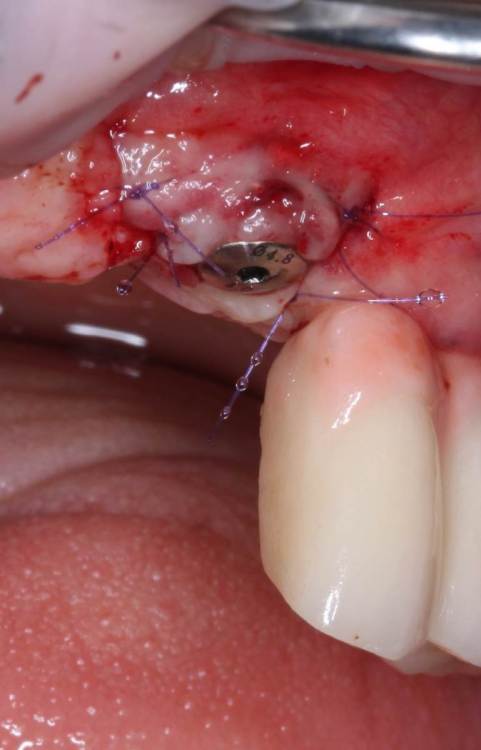

АнтонТЛТ Опубликовано 4 июня, 2021 Поделиться Опубликовано 4 июня, 2021 Жил да был имплантат 3.5мм, прижимался хорошо вместе с поджсаженной костью. Но в один момент ортопед со злобным техником решили его запротезтровать неоригинальным тибейсом в составе цирконевого моста. Имплантату это не понравилось и он решил, что ему пора на покой. И сделал себе харакири. А чтобы не сильно травмировать пациента, было решено удалить винт и имплантат. Затем сразу же поставить имплантат чуть короче и немного потолще. Время работы 50минут с учётом фотографий. 3 Ссылка на комментарий

АнтонТЛТ Опубликовано 4 июня, 2021 Автор Поделиться Опубликовано 4 июня, 2021 1 час назад, Irouil сказал: Винт, насколько я понимаю, удалялся реверсивным сверлом. А чем удалялся сам имплант? Fr-kit neobiotech 1 Ссылка на комментарий